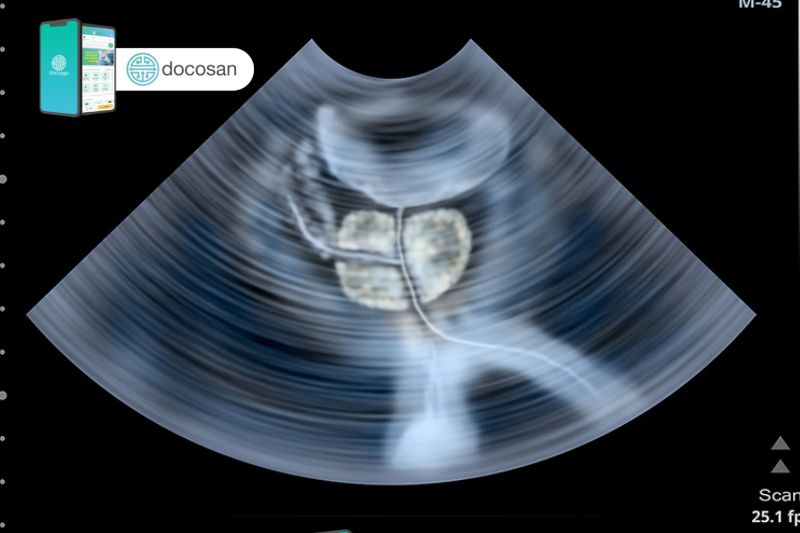

Kích thước của tuyến tiền liệt trưởng thành bình thường là khoảng 25 đến 30mm chiều ngang, 30 đến 35mm chiều dọc, 25 đến 30mm chiều trước sau và trọng lượng trung bình 15 đến 25g. Khi độ tuổi càng tăng thì kích thước cũng như trọng lượng này cũng cao lên.

Các phép đo kích thước phì đại tiền liệt tuyến cần có độ chính xác cao để xác định được giai đoạn tiến triển của bệnh và quyết định phương pháp, cho nên người mắc bệnh nên đến các cơ sở y tế uy tín gặp bác sĩ nam khoa có tay nghề để thăm khám và được làm xét nghiệm trước khi điều trị.

Đánh giá kích thước phì đại tiền liệt tuyến theo từng giai đoạn là bước rất quan trọng để xác định chẩn đoán mức độ của bệnh để từ đó chọn lựa biện pháp điều trị tối ưu. Vậy nên nếu bạn đang gặp phải các dấu hiệu của bệnh thì hãy đi khám bác sĩ nam khoa càng sớm càng tốt. Bạn sẽ được thăm khám kỹ lưỡng và thực hiện các xét nghiệm cần thiết để xác định rõ được kích thước phì đại tiền liệt tuyến.